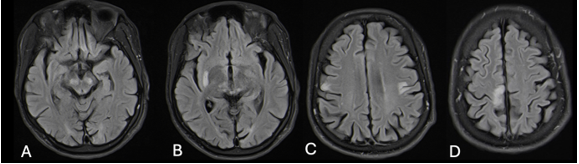

A 28-year-old male presented to the neurology unit at Inkosi Albert Luthuli Central Hospital with a ten-year history of progressively worsening bilateral tonic-clonic seizures, facial twitching, upper limb jerks and cognitive decline. He had a normal birth history and developmental milestones. He had been well prior to age 18, with no previous history of a hypoxic event or trauma. There was no family history of note. On social history, he had previously worked as a taxi driver and was a cigarette smoker with a 14 pack-year history. He drank alcohol on social occasions but did not have a history of illicit drug use. Despite being commenced on adequate doses of sodium valproate and carbamazepine by his district hospital, there was no improvement in seizure frequency. On examination he was noted to have mild cognitive impairment and a scanning dysarthria. Continuous focal movements of the right orbicularis oris and left orbicularis oculi were seen. He was observed to have stimulus-sensitive and action myoclonus of the right upper limb, as well as negative myoclonus. He was quadrispastic and had bilateral cerebellar dysfunction. His fundus examination was normal (with no cherry-red spot seen). Whilst in the ward, he was observed to have behavioural problems, having verbal and at times, physical, altercations with other patients in the neurology ward. In summary, this was a 28-year male patient who presented with features of a progressive myoclonic epilepsy (PME). On investigation his serological markers revealed normal urea and electrolytes, liver function and full blood count. Anti-nuclear factor and autoimmune encephalitis panel were negative. Metabolic screen including thyroid function, vitamin B12 (340 pmol/L) and lipid profile were normal. His serum lactate was normal (1.5 mmol/L). Sodium valproate and carbamazepine levels were within therapeutic range. Inflammatory markers were normal, while an infective screen including HIV, syphilis, herpes simplex virus and hepatitis were negative. Lumbar puncture revealed normal chemistry and was negative for herpes simplex virus, varicella-zoster virus, GeneXpert, syphilis and cryptococcus. His EEG revealed a slow background but no epileptiform activity. MRI brain showed multiple focal hyperintensities in the cortex as well as the thalami, midbrain and putamina (Figure 1). With no clear aetiology established, an axillary skin biopsy was performed. Histology revealed pathognomonic Lafora bodies in the sweat gland luminal cell layer. These are illustrated in Figure 2 as violet inclusion bodies after periodic acid Schiff (PAS+) staining.

Figure 1: Note multiple focal hyperintensities in the midbrain (A), thalami (B), putamina (B) and cortical regions (C, D).